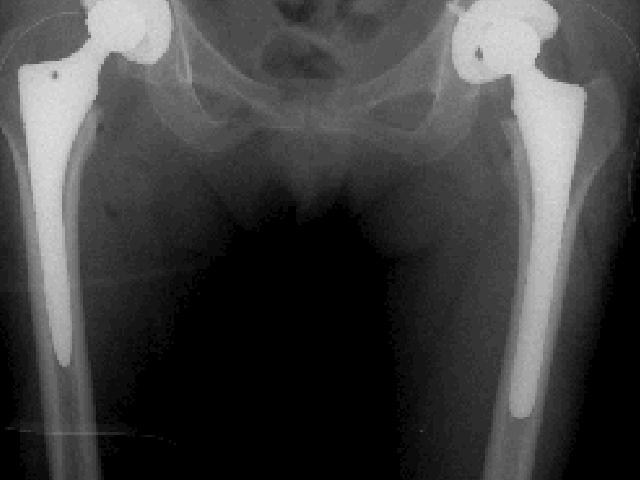

これが今回のレントゲン。。

4年前とチョッと変わっているような。。。

右と左の長さが違いますね。。

この人工関節は15年ほどで交換するのですが。。

右は後11年か。。。

拓ママ見事に50代になってるんだろうな。。。